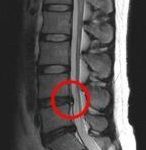

腰痛

みたちカイロプラクティック整体院では腰痛で通われる方が一番多 …